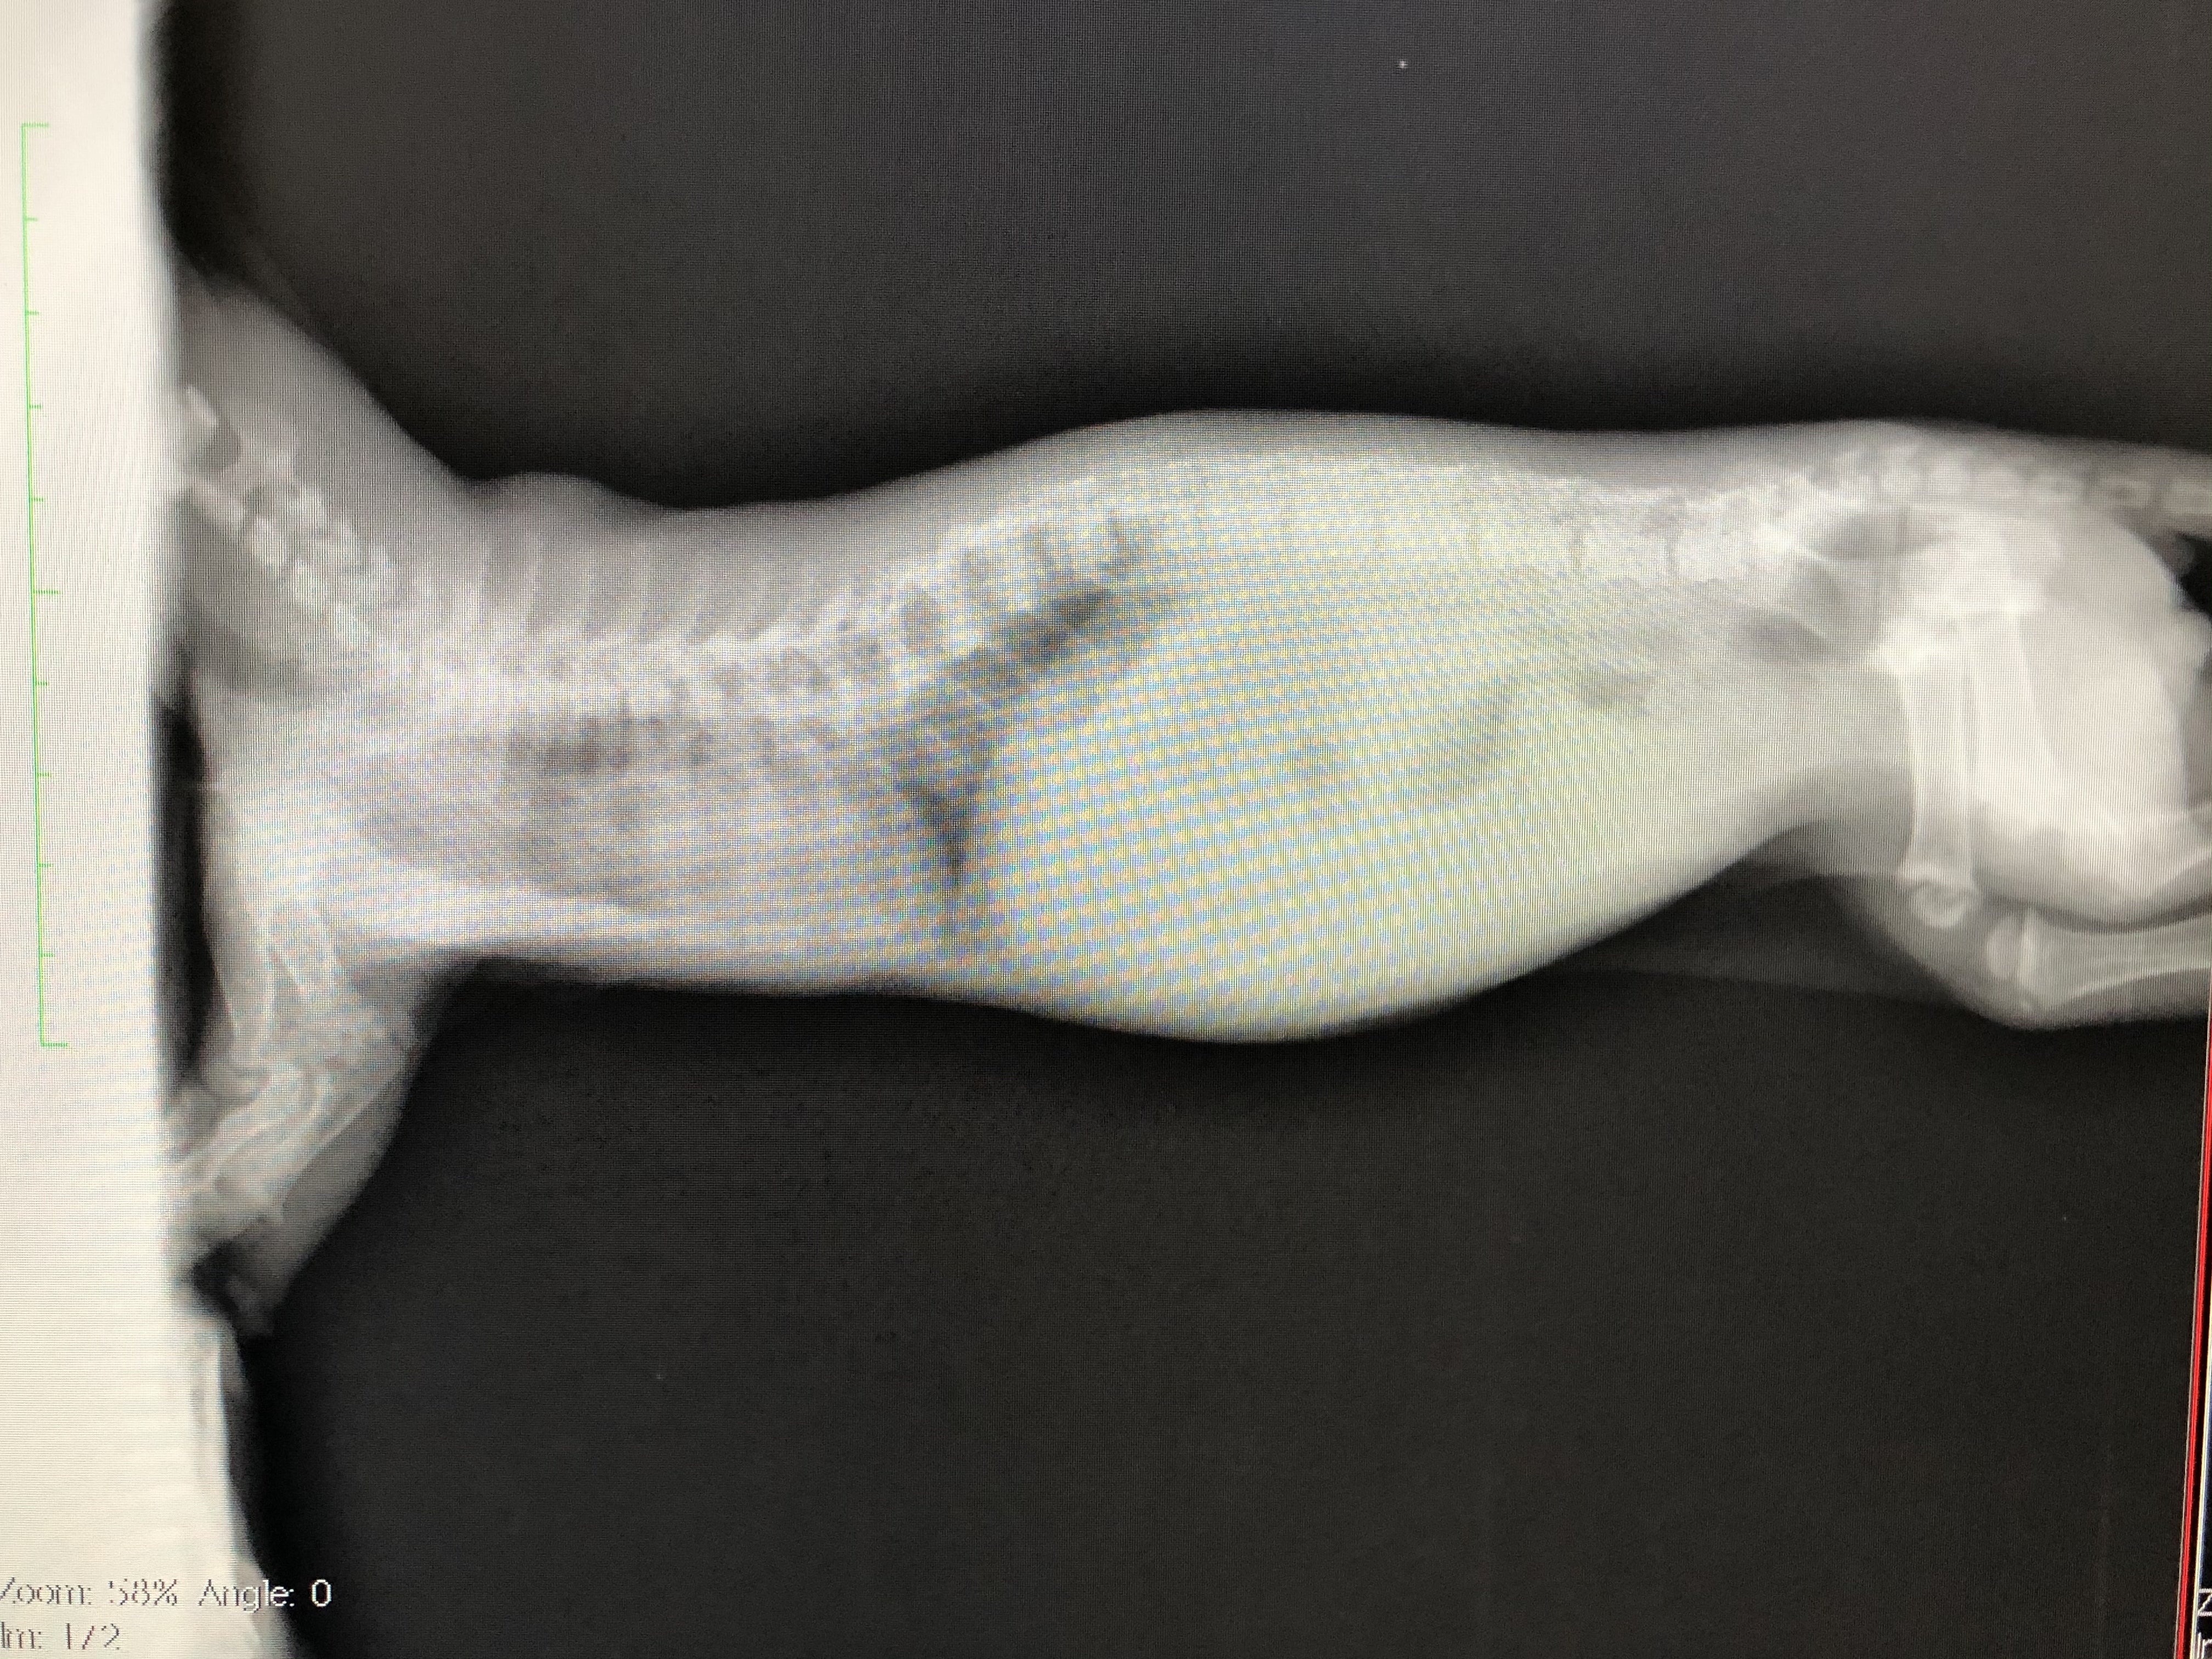

肋骨変形に伴う脊椎側変症

先天的な骨格異常で背骨と肋骨が変形していると診断されました。

また、この骨格異常により、肋骨と背骨の間のスペースが狭く、このまま成長していくと心臓と肺が圧迫され最悪生きられないと言われました。

レントゲン、CT撮影で費用が嵩む上、成長過程のため、複数回必要とのこと。これらを総合し、合計150万円〜は用意しておいて下さいと言われました。